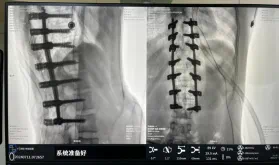

圖為置釘后

據(jù)悉脊柱側(cè)彎手術(shù)治療后可以保持軀干平衡,改善外觀并防止畸形進(jìn)一步發(fā)展。患者的生活質(zhì)量得到提高,進(jìn)而減少脊柱過(guò)度畸形可能帶來(lái)的疾病的發(fā)生率,外觀上的積極變化往往也能帶來(lái)患者心理與精神的積極變化。臨床上會(huì)綜合考慮患者的年齡、側(cè)彎程度、進(jìn)展趨勢(shì)、骨質(zhì)條件、鄰近節(jié)段情況、手術(shù)節(jié)段等因素,合理采用個(gè)性化的手術(shù)方式進(jìn)行治療。然而,由于脊柱神經(jīng)血管密布,手術(shù)操作相對(duì)復(fù)雜,手術(shù)難度高、風(fēng)險(xiǎn)大,傳統(tǒng)脊柱側(cè)彎的手術(shù)方式往往有較高的神經(jīng)或脊髓損傷風(fēng)險(xiǎn)。故此次科室決定開展機(jī)器人輔助導(dǎo)航下脊柱側(cè)彎矯形、植骨融合內(nèi)固定手術(shù)。術(shù)前,醫(yī)生團(tuán)隊(duì)在機(jī)器人多維度圖像融合智能手術(shù)規(guī)劃功能的輔助下,預(yù)先規(guī)劃了理想的置釘路徑。術(shù)中,天璣骨科手術(shù)機(jī)器人準(zhǔn)確遵循術(shù)前規(guī)劃,根據(jù)配準(zhǔn)結(jié)果,實(shí)時(shí)定位并準(zhǔn)確執(zhí)行置釘操作,所有導(dǎo)針均用電鉆置入,一次性成功,協(xié)助醫(yī)生順利完成手術(shù)。最終,在麻醉科、手術(shù)室密切配合下,歷時(shí)3小時(shí)成功完成側(cè)彎矯形術(shù),出血量?jī)H500ml。術(shù)后,患者恢復(fù)良好,大小便及下肢神經(jīng)運(yùn)動(dòng)感覺(jué)正常。